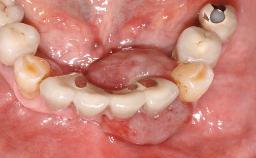

A 27-year-old male was referred to the periodontist for assessment and management of implant site 41. The implant had been placed nine years previously and restored with a screw-retained single crown. The patient was a cigarette smoker in good general health. He reported he had reduced his smoking habit from 25 cigarettes per day to 15 cigarettes per day in the previous six months. On examination, there was calculus and plaque present at the lower anterior teeth and at implant site 41. Localized attachment loss was observed at teeth 32 and 42, with 2–3 mm of gingival recession. At implant site 41, there were 8–9 mm probing depths with suppuration and bleeding on probing.